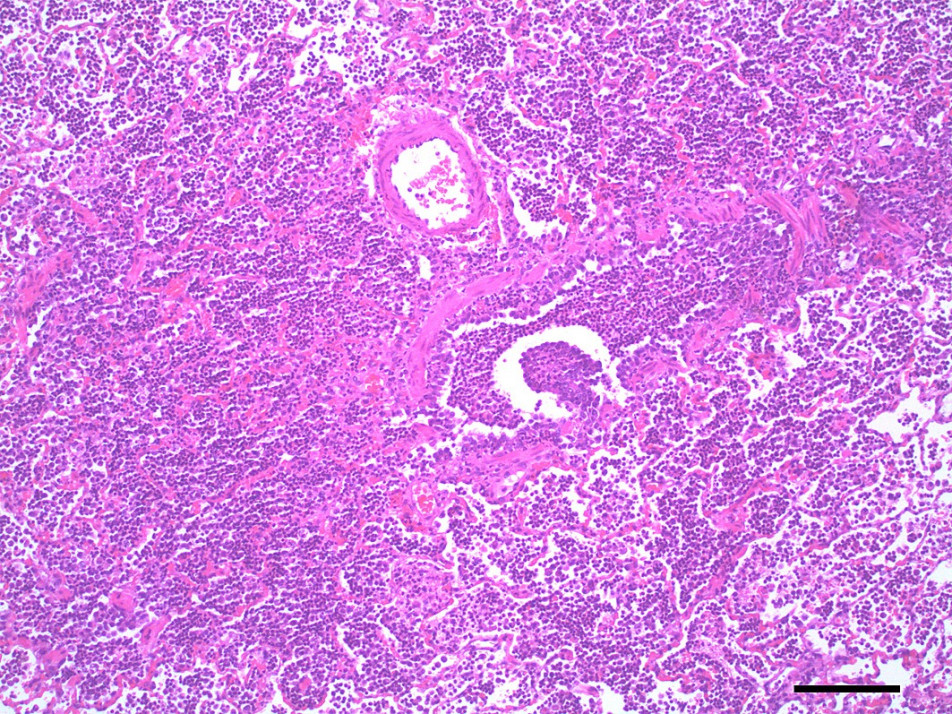

Antibiotics would appear to be useful for management of existing aspiration pneumonia in paralysed animals. Evidence for this was found in the post-mortem examination of 25 dogs that had severe respiratory failure in which all dogs had histological lung changes and 15/25 had bronchopneumonia (Webster et al., 2013b).

Pulmonary oedema and congestion were noted in 36% (9/25) dogs euthanised for tick paralysis and this probably contributes to the development the hypoxaemia observed in some patients (Webster et al., 2013b)(Figure 5,6). Pulmonary oedema is a consistent finding in animals affected with tick paralysis. Left lateral chest xrays of 75 dogs presenting with tick toxicity revealed that 38% had signs of pulmonary congestion manifest as pulmonary vein dilation placing them at risk of developing pulmonary oedema (Day and Schull, 2008). It is unclear what the pathophysiology of this process is but it is an ongoing area of research interest (Webster, 2014a). Treatment of pulmonary oedema with diuretics may appear logical but diuretics raise the potential for other fluid therapy complications and has not be recommended for management of pulmonary oedema from tick paralysis (Webster, 2014b). The investigation of cardiac biomarkers in dogs with tick paralysis provides further evidence that the pulmonary oedema is non-cardiac in origin (Nicolson et al., 2016).